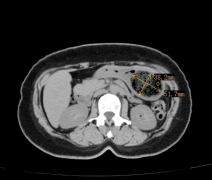

静脉曲张,作为一种极为常见且不容忽视的血管疾病,它在我们的日常生活中其实并不鲜见。那些蜿蜒、扩张,仿若蚯蚓般盘踞在腿部肌肤之下的青筋,不仅影响着肢体外观,更给患者带来了或轻或重的不适乃至疼痛,严重干扰着日常行动与生活质量。

静脉曲张是因为血液淤滞,长期血管压力大导致静脉壁薄弱而引起的疾病。主要表现为静脉出现扩张、迂曲。而男性和女性的静脉结构并没有明显的差异,因此男性同样会患上静脉曲张。